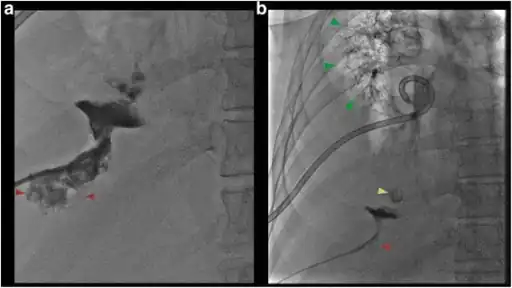

a) Fluoroscopic view shows contrast in collapsed liver abscess red arrow b) fluoroscopic view shows contrast tracking from the liver abscess red arrow

A large pyogenic liver abscess presumed to be the result of appendicitis